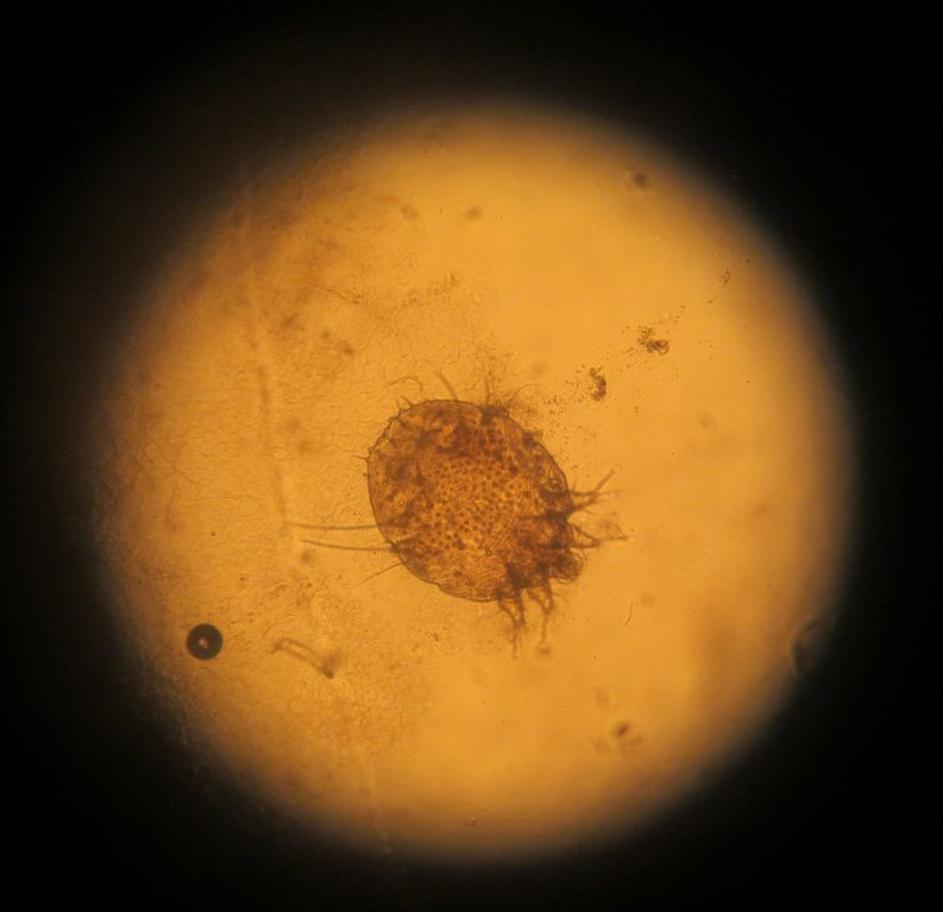

V slovenski šoli so se pojavile garje

Garje Shutterstock Garje